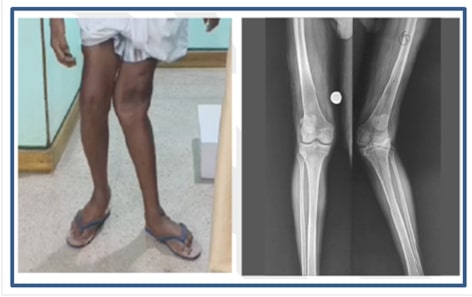

Valgus knee deformity, commonly referred to as an “X-shaped leg”, occurs when the knee bends inward while the lower leg points outward. In severe cases, this condition can be disabling.

Knee angulation of 32 degrees inward

Before Surgery